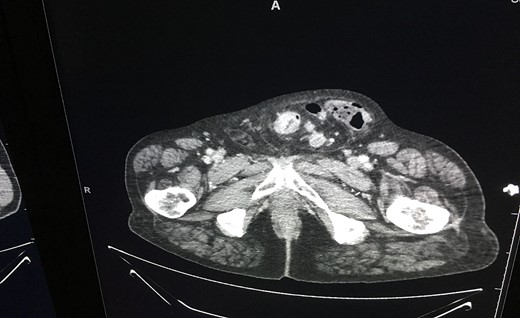

An ultrasound of the scrotum revealed ‘large left inguinal scrotal hernia containing omentum and bowel loops, on the right a high indirect inguinal hernia containing only fat tissue’ was described. A CT was subsequently performed, which revealed a likely primary sigmoid colon malignancy lying within the left-sided scrotal hernia and extensive liver metastasis (as seen in Fig. 2). The tumour contained within the hernia sac is illustrated in Fig. 3.

This case emphasizes the important role of imaging as an adjunct to diagnosis and aid to preoperative planning. In the absence of imaging, a surgical team could be faced with a far more challenging operation than expected as the cancer would not have been identified pre op. A hernia repair that has the potential to turn into a cancer resection needs appropriate surgical expertise present at the time of the operation in order to manage the case appropriately.

In this case, a preoperative CT scan allowed for discussion at the MDT meeting and appropriate planning prior to the operation to be undertaken. Furthermore, the radiological diagnosis allowed this particular person to weigh up all options preprocedure. Ultimately, it is of the utmost of importance that a patient should be involved at every step of his/her treatment journey so the more information they can be given to guide their decisions, the better the outcomes.